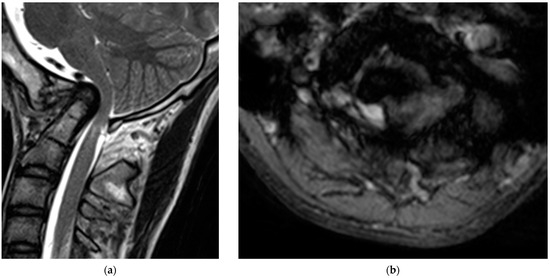

Radiological examinations demonstrated the abnormalities of the craniocervical junction and fusion of C2/3. Scoliosis in the cervicothoracic region was also confirmed. Computer tomography (CT) scans revealed the assimilation of the occiput with the atlas and posterior deviation of the odontoid process, which was invaginated into the foramen magnum (Figure 1). Magnetic resonance imaging (MRI) demonstrated severe ventral compression of the medulla oblongata and the spinal cord (Figure 2).

Figure 2. Preoperative magnetic resonance images: (a) sagittal; (b) axial view of the T2-weighted images.